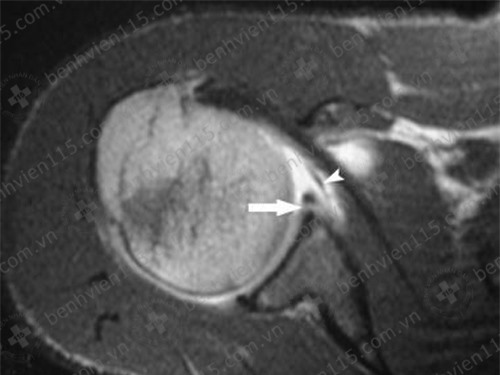

Ảnh chụp MRI cho thấy rách sụn viền vai phải, tổn thương Bankart sụn